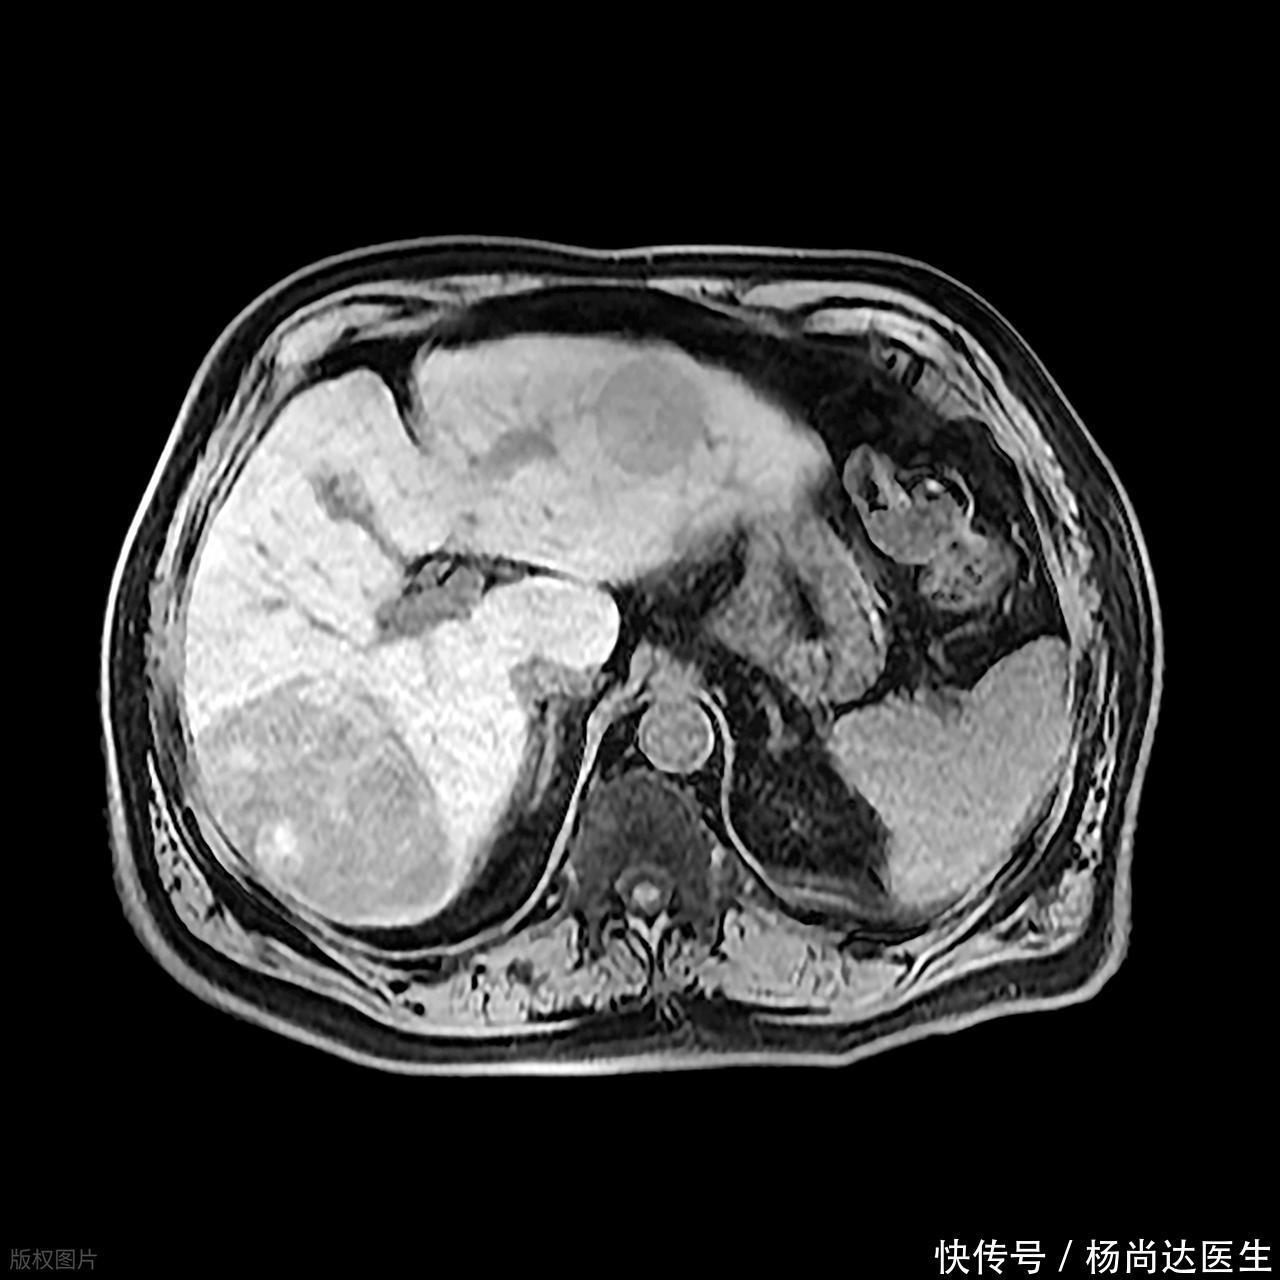

它们也许只是在超声或CT上展现出比周围肝组织略微低一点的密度,像是给图片打了个浅浅的阴影,旁边还带着些许模糊的过渡地带,这不像是那种边界清晰的肿瘤,反而让人觉得更像炎症的痕迹。

更有甚者,在增强扫描的特定时期,那些本该被明显染色的区域,却像海绵吸水一样,吸收得慢吞吞的,或者在很晚的延迟期才慢慢显现出一些不均匀的强化,这种“慢热”的表现,恰恰提示着局部组织结构可能已经被破坏。

医生在报告上写下“周边可见少量液化征象”,这句话听起来技术性十足,但本质上就是警告,那个看起来像水的地方,可能不是结构水囊,而是正在发酵的感染灶,它在悄悄地“溶解”肝脏的正常结构。

区分的关键点,往往隐藏在动态变化和细微的边界处理上,良性的单纯囊肿,边缘是光滑的,内部回声均匀得像一汪清水,而早期的感染灶,往往在边界处有类似“毛刺”的结构,或者在特定的造影剂作用下,它周边的肝组织会显示出高血管性的反应,这种“边上的激动反应”,是单纯囊肿所不具备的征象,反映出机体正在对入侵物发起一场局部战斗。